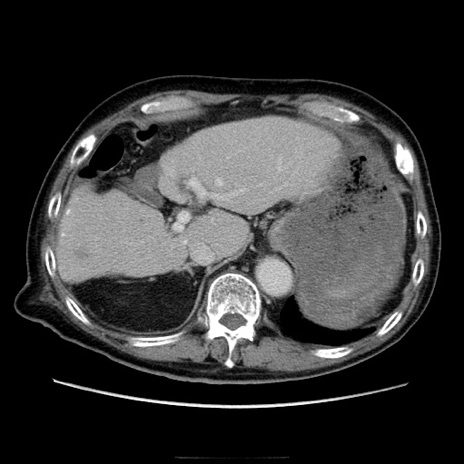

症例21(横断像)

【症例】70歳代男性

【主訴】腹痛

【現病歴】肝硬変・肝細胞癌にてかかりつけの方。約9時間前に食後より腹痛出現。症状が徐々に増悪し、嘔吐出現したため来院。

【既往歴】肝硬変、肝細胞癌(RFA、TACE後)

【身体所見】意識清明、表情苦悶様、BT 36℃、BP 129/78mmHg、P 88bpm、SpO2 97%(RA)、右上腹部から心窩部にかけて圧痛あり、反跳痛なし、筋性防御あり。

【データ】WBC 5800、CRP 0.16